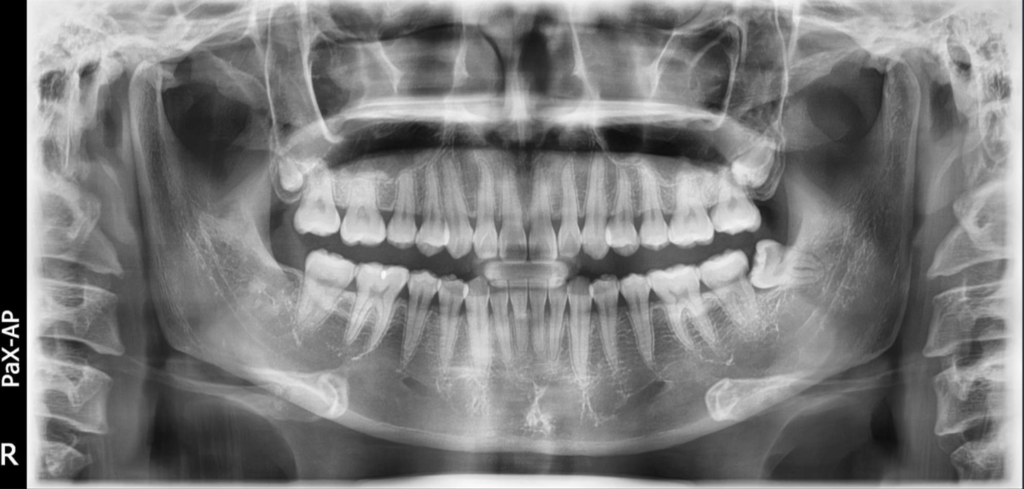

FOV DE ARCO EXTENDIDO

El innovador FOV de Smart Plus proporciona un volumen en forma de arco, que muestra una vista más amplia de la dentición en comparación con otros dispositivos del mismo campo de visión. Para los terceros molares, existe una alta posibilidad de que el diente se corte de la imagen. El “FOV de arco extendido” elimina esta posibilidad y proporciona al médico toda la dentición necesaria para un diagnóstico completo.